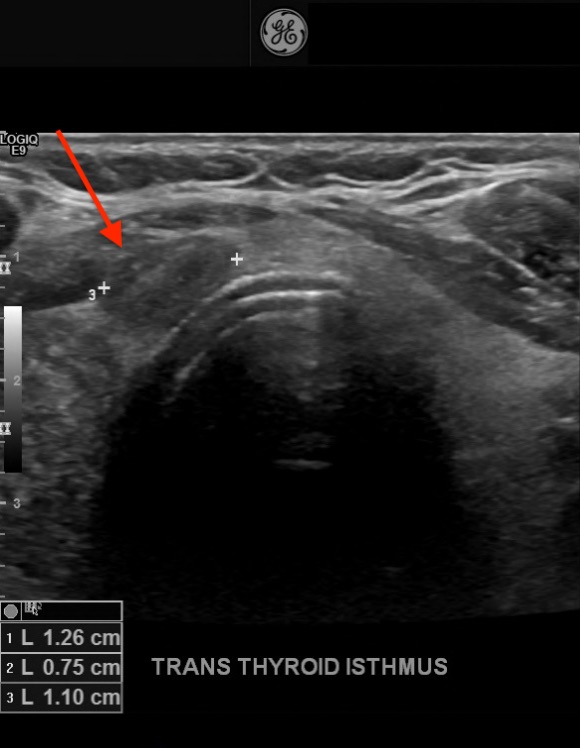

Diagnostic tests. His thyrotropin level was normal (0.495 mIU/L; reference range, 0.49-4.67 mIU/L). Findings of initial neck US performed at an outside hospital identified a solitary right thyroid nodule. Repeated US revealed 3 nodules that were greater than 1 cm in diameter and a few subcentimeter-sized nodules. In the central aspect of the right lobe was an ill-defined, 3.1-cm, heterogeneous, isoechoic solid nodule with mildly irregular margins, microcalcifications, a taller-than-wide shape, and increased vascularity (Figure 1). In the left aspect of the isthmus was a well-circumscribed, 1.3-cm, ovoid solid nodule with internal microcalcifications, a wider-than-tall shape, and peripheral vascularity (Figure 2).

Figure 2. A 1.3-cm, well-circumscribed, solid nodule (arrow) with microcalcifications and a wider-than-tall shape in the isthmus of the thyroid.